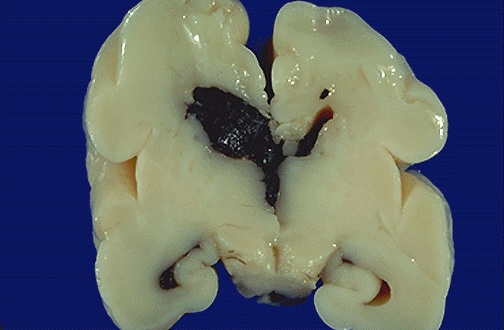

| This coronal section of a premature neonatal brain shows intraventricular hemorrhage (IVH) extending from a germinal matrix hemorrhage. Such hemorrhages occur from a variety of factors that afflict neonates, including difficulty regulating blood pressure. Such hemorrhages can be devastating. |